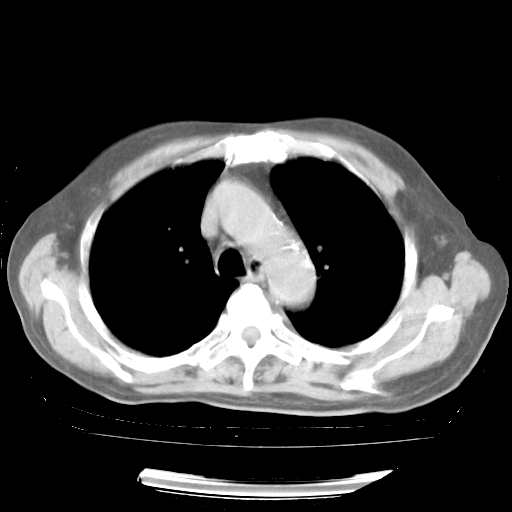

4月28日肺部CT——再次出现类似去年5月9日——透光度降低,“间质性”改变。

4月28日肺部CT——再次出现类似去年5月9日——磨玻璃样、间有“粟粒样”改变。